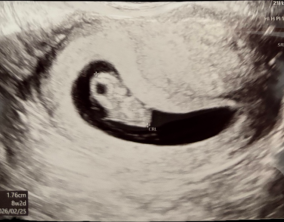

눈물로 실감한 아홉 번째 주

이경훈 원장님은 검사를 통해 나온 수치와 결과에 대해 자세히 설명해 주시고, 상황에 맞는 여러 방법을 함께 제시해 주셔서 큰 신뢰와 감사함을 느꼈습니다. 불안을 혼자 짊어지…